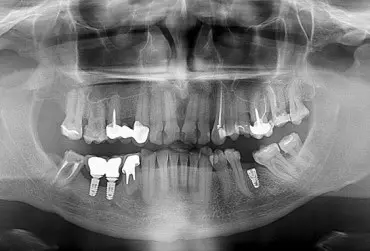

Eksplantacja uszkodzonego implantu zębowego u pacjenta obciążonego kardiologicznie – czy to się może zdarzyć?

Implanty zębowe są coraz popularniejsze w leczeniu stomatologicznym. Zdarza się, że pacjenci uważają je za niezniszczalne. Tymczasem na implanty działają różne siły i przeciążenia mogące powodować ich dysfunkcje. W niniejszym artykule przedstawiono przypadek pacjenta z uszkodzonym implantem zębowym. Dodatkowo pacjent był obciążony kardiologicznie, co wymagało wzmożonej ostrożności w procesie leczenia implantoprotetycznego.